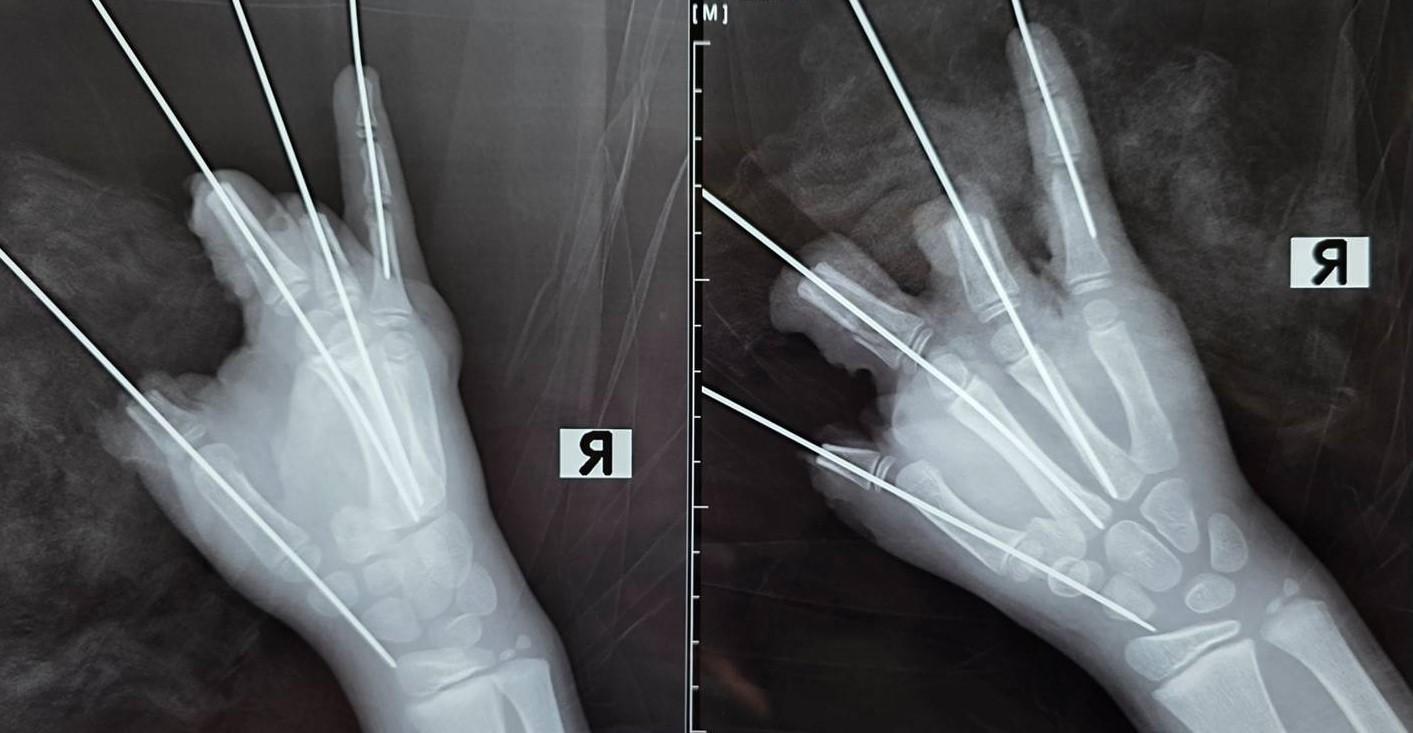

В Санкт-Петербургском государственном педиатрическом медицинском университете уточнили характер травм. У ребенка ампутировало четыре пальца — с большого по безымянный — и сильно пострадал мизинец. Также зафиксированы открытый перелом и вывих пястной кости, размозжение и множественные дефекты мягких тканей правой кисти.

Мальчика доставили в клинику университета в 21:40 и сразу прооперировали. В настоящее время он находится в реанимации. Медики отмечают, что в ближайшие дни возможна некротизация части тканей кисти, что характерно для подобных травм.